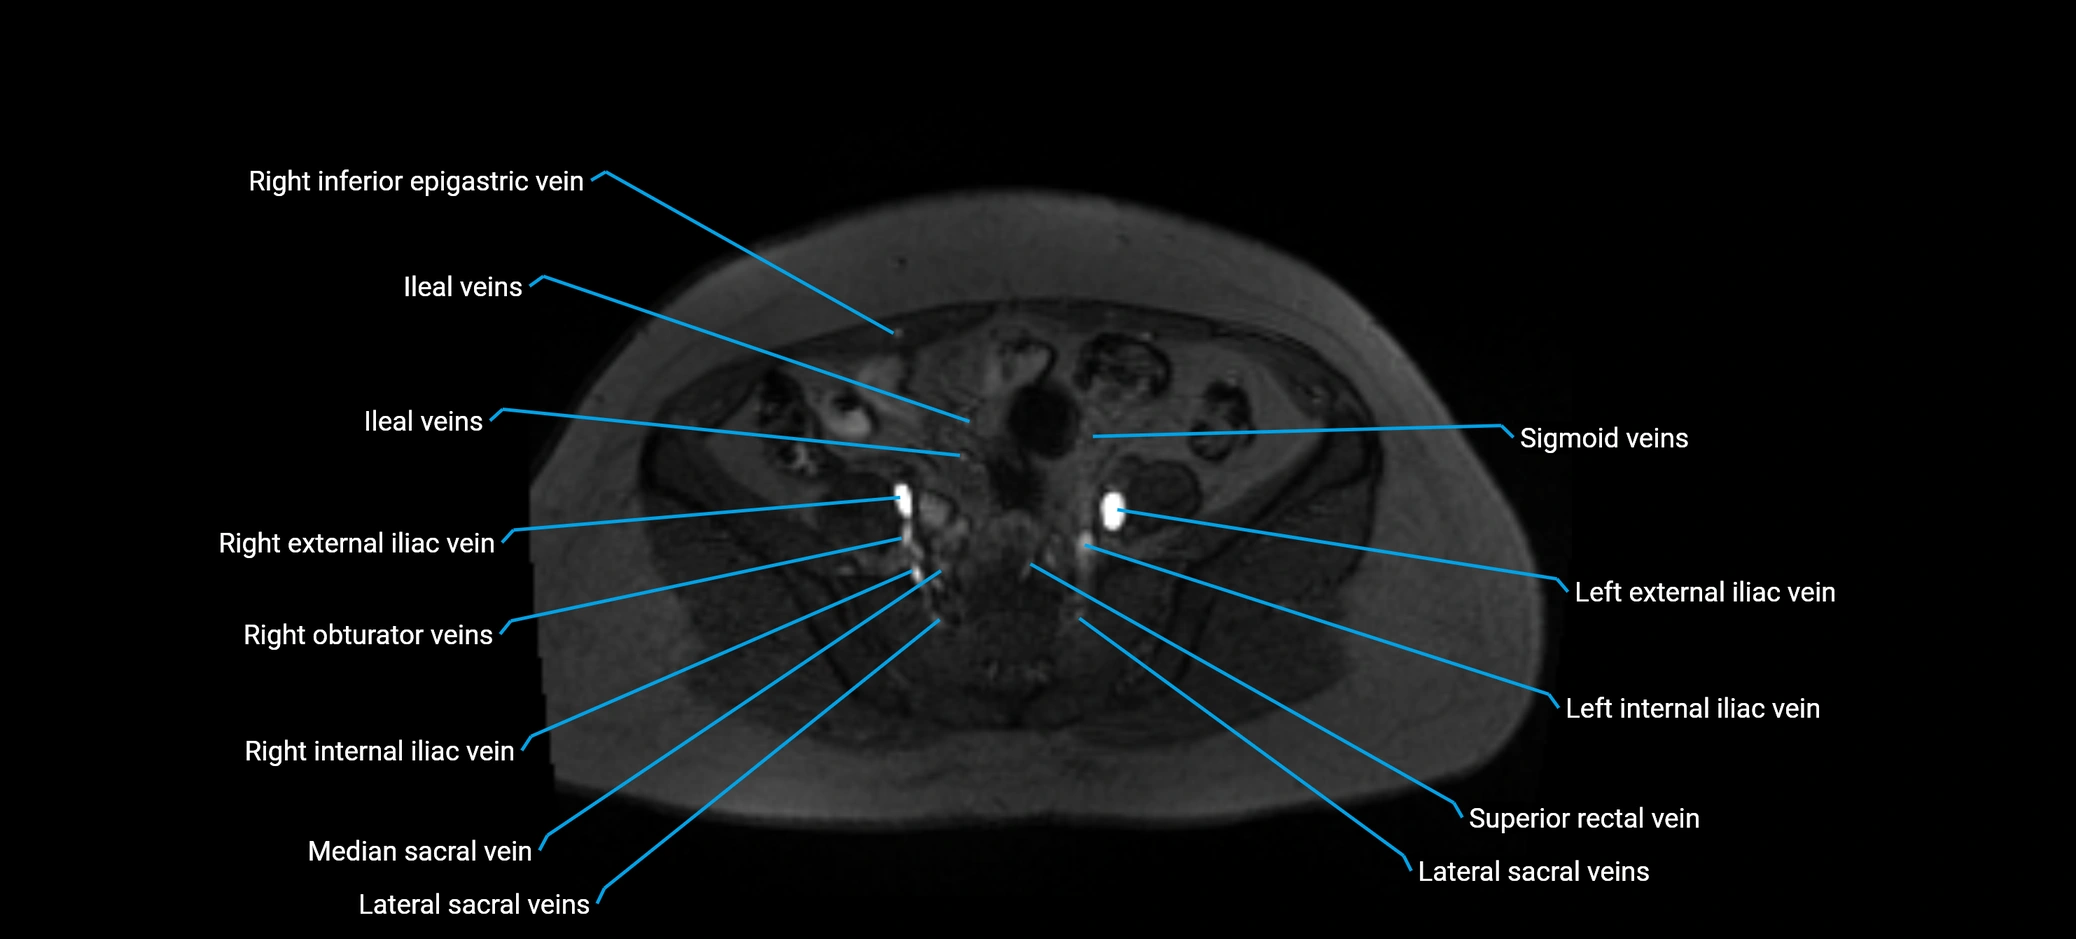

MRI image

image